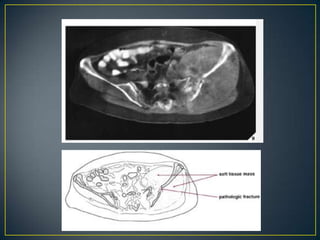

• Benign tumors and tumor-like bone lesions usually do not

exhibit soft-tissue extension; thus, almost invariably, a

soft-tissue mass indicates an aggressive lesion and one

that is in many instances malignant .

• With few exceptions—such as giant cell

tumors, aneurysmal bone cysts, osteoblastomas, or

desmoplastic fibromas.

• In the case of a bone lesion associated with a soft-tissue

mass, it is always helpful to determine which condition

arose first.